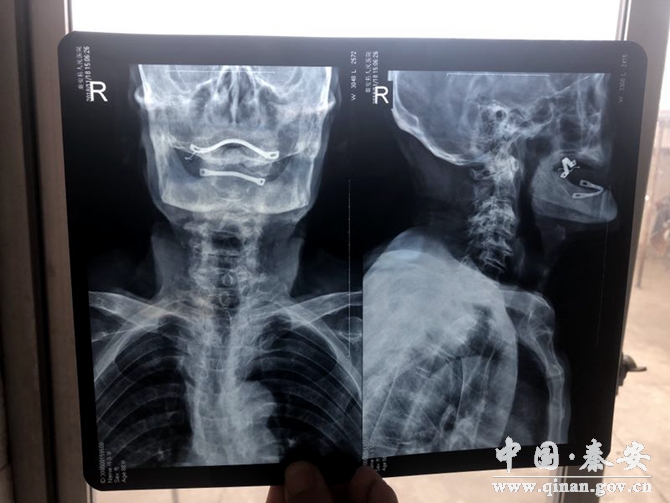

其中一位72歲女性住院患者,主因“頸部不適伴頭昏頭暈3年余,加重1天”收住。無高血壓,冠心病病史。平時(shí)不能坐立看電視,不能俯臥。服藥兩年,沒有明顯效果,來診后應(yīng)用針刀微創(chuàng)治療,松解減壓,病人頭昏頭暈明顯減輕,偏頭痛基本消失。

目前頸椎病的保守治療較多,但見效較慢,療效甚微,針刀閉合松解術(shù)的出現(xiàn),給頸椎病患者帶來了福音,針刀直接解除頸部病變組織的瘢痕,粘連、攣縮、堵塞,使頸段脊柱生物力學(xué)平衡得到有效恢復(fù),解除對神經(jīng)根及椎動脈的刺激,則疼痛、眩暈等癥狀緩解或消除,治療過程操作簡單,見效快,切口小,痛苦少,治療效果明顯,避免西藥對人體的危害。